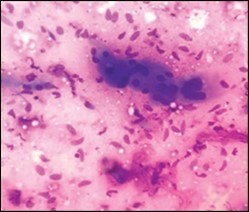

On gross examination, a tan coloured, gritty nodule, confined to the sternocleidomastoid muscle is delineated. Characteristically, smears obtained by fine needle aspiration cytology are composed of bland appearing, plump or normal fibroblasts and proliferating fibroblasts with an admixture of degenerative, atrophic skeletal muscle cells, giant myocytes with several nuclei, scattered, bare, bland nuclei or cells with fragmented, wispy cytoplasm and parallel aggregates of fibroblasts. The background is clear and devoid of cellular or nuclear debris. Sheets of spindle-shaped fibroblasts, atrophic muscle fibres and regenerating, multinucleated muscle giant cells are intermingled with the fibroblastic component 5, 6.

Figure 4.Fine needle aspiration cytology of fibromatosis colli delineating aggregates of plump, spindle-shaped cells admixed with fibroblasts, fibro-connective tissue fragments and intermingled red cell extravasation 11

Figure 5.Fine needle aspiration cytology of fibromatosis colli exhibiting aggregates of spindle- shaped cells, plump fibroblasts, fibro-connective tissue fragments and a clear background with minimal red cell extravasation 12.